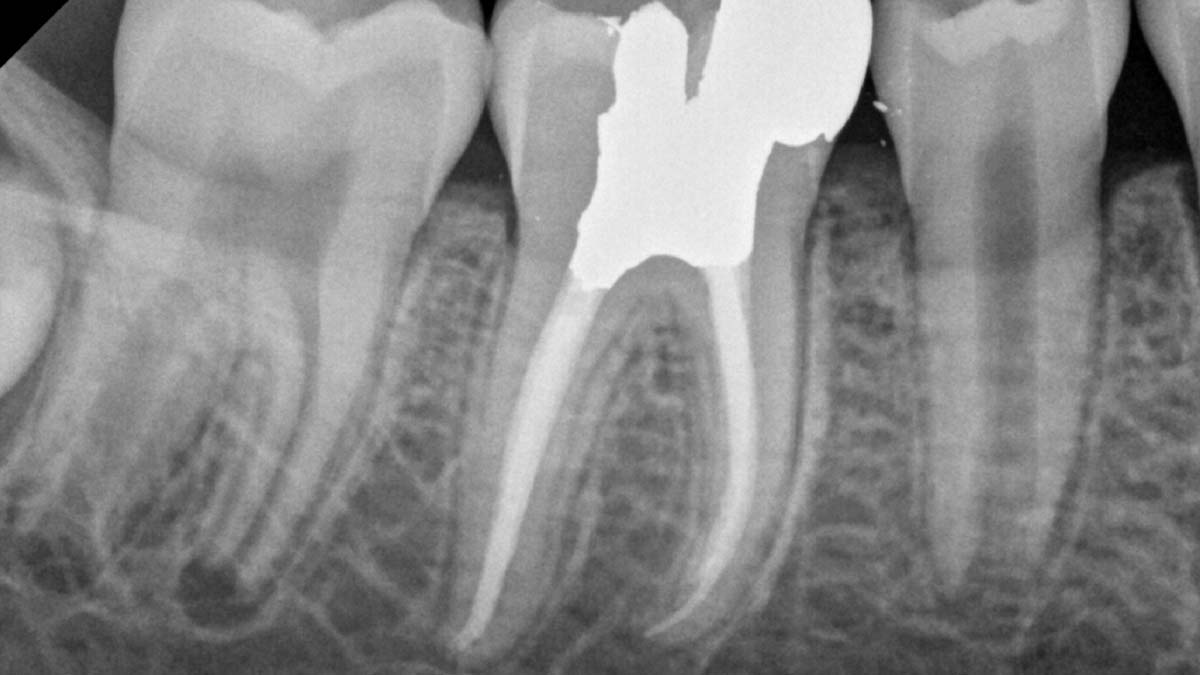

Links: Die Verwendung verschiedener Formulierungen von Guttapercha kann zu unterschiedlicher Opazität führen.

Bild mit freundlicher Genehmigung von Dr. Phillip Bell, Mooresville, NC